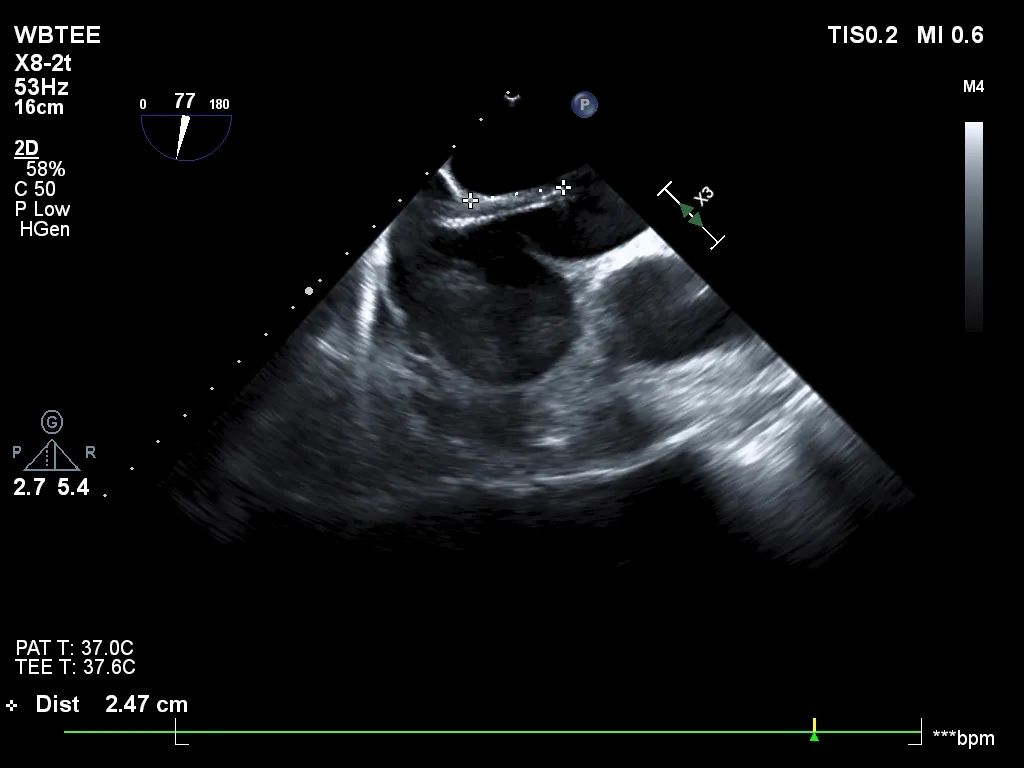

术前行经食道超声评估

原发性二尖瓣反流,反流程度4+;二尖瓣瓣口面积4.15cm²,平均跨瓣压差5mmHg,二尖瓣前叶(A2)长度23.35mm,二尖瓣后叶长度(P2)长度13.2mm;左室射血分数67%。患者手术风险高,操作难度大,经心脏瓣膜团队多次充分讨论评估后,决定行经导管二尖瓣缘对缘修复治疗。

术前MDT策略:从解剖结构来看二尖瓣后叶脱垂伴连枷涉及整个2区,累及3区和1区,宽度15mm左右,且连枷高度甩起高度有7-8mm,可见长达10.4mm的飘样回声,术前策略预计使用两个二尖瓣夹,较小的二尖瓣口面积和较高平均跨瓣压差,是一次高难度的挑战。